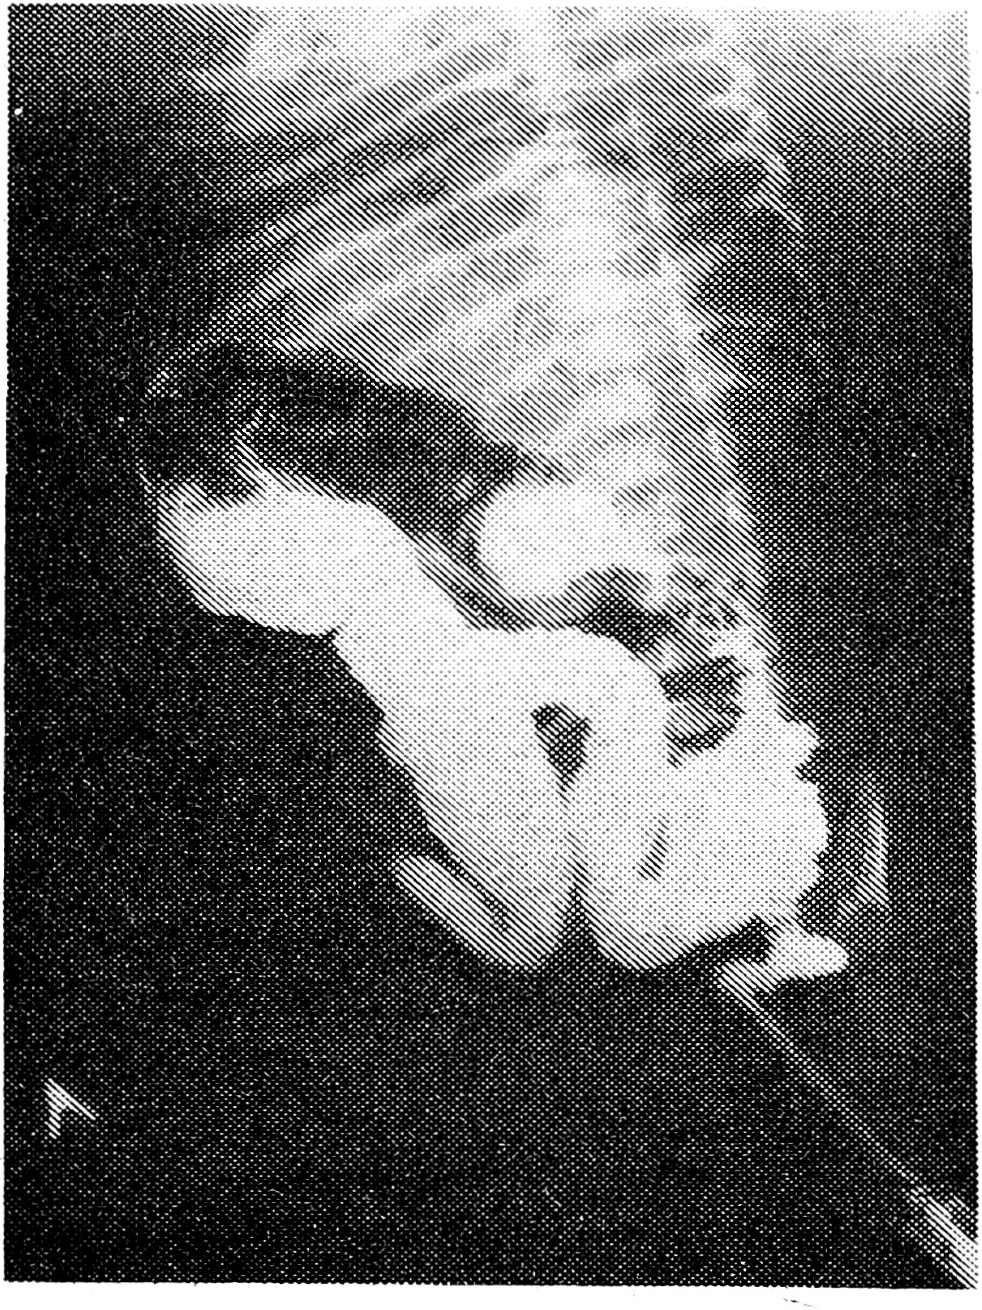

Основными клиническими симптомами при атрезиях пищевода являлось обильное истечение изо рта и носа новорожденного ели зи и слюны (у 13); рвота после первого корм ления несвернувшимся молоком, сопровождав шаяся приступами кашля и цианоза (у 15). При рентгенологическом обледоваиии этих детей контрастированием йодолиполом (1,0 мл) через введенный резиновый катетер в 19 из 20 случаев были выявлены различные типы атрезий с трахеопищеводными свищами и наличием газа в пищеварительном тракте. У 17 из них были признаки аспирационной лиев монии, у 3 детей симптомы атрезии пищевода сочетались с врожденным пороком сердца. У одного ребенка с атрезией проксимального конца пищевода без фистулы с трахеей обзор I ная рентгенография органов грудной и брюшной полости показала полное отсутствие газа в пищеварительном тракте. Для иллюстрации приводим рентгенограмму ребенка с атрезией пищевода (рис. 1).

Рис. 1. На обзорной рентгенограмме органов грудной и брюшной полости после введения через резиновый катетер 1 мл йодолипола определяется атрезия проксимального отрезка пищевода. Наличие газа в петлях кишечника указывает на трахеопищеводный свищ дистального отрезка пищевода.